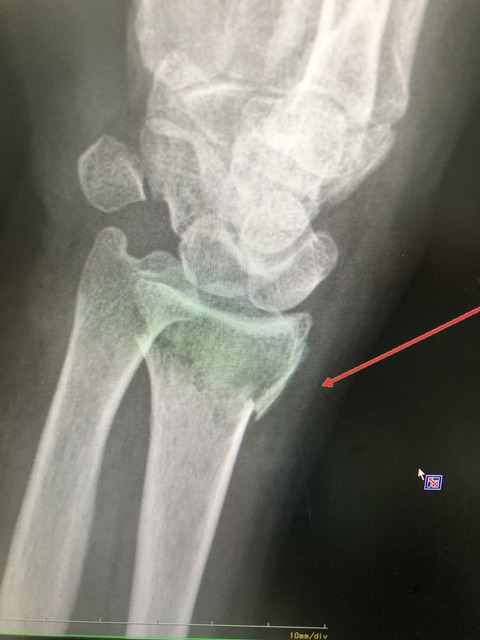

野球アスリートで多い骨折が

この 有鈎骨骨折です

レントゲンでも診断つきますが、

わかりにくいため、CTで精密検査します

ほっておくと、偽関節になり しびれ、

力が入らなくなるため、注意が必要です。

他で、診断つかず

偽関節になって来院されました

6AAF758A-4280-4B98-89C3-FB116E6DC88B

9190420E-589A-4820-9734-CE51A8BB09DA

何とかスポーツ活動できているので、

本人の希望で、

手術も視野にいれ、保存的に治療していきます。